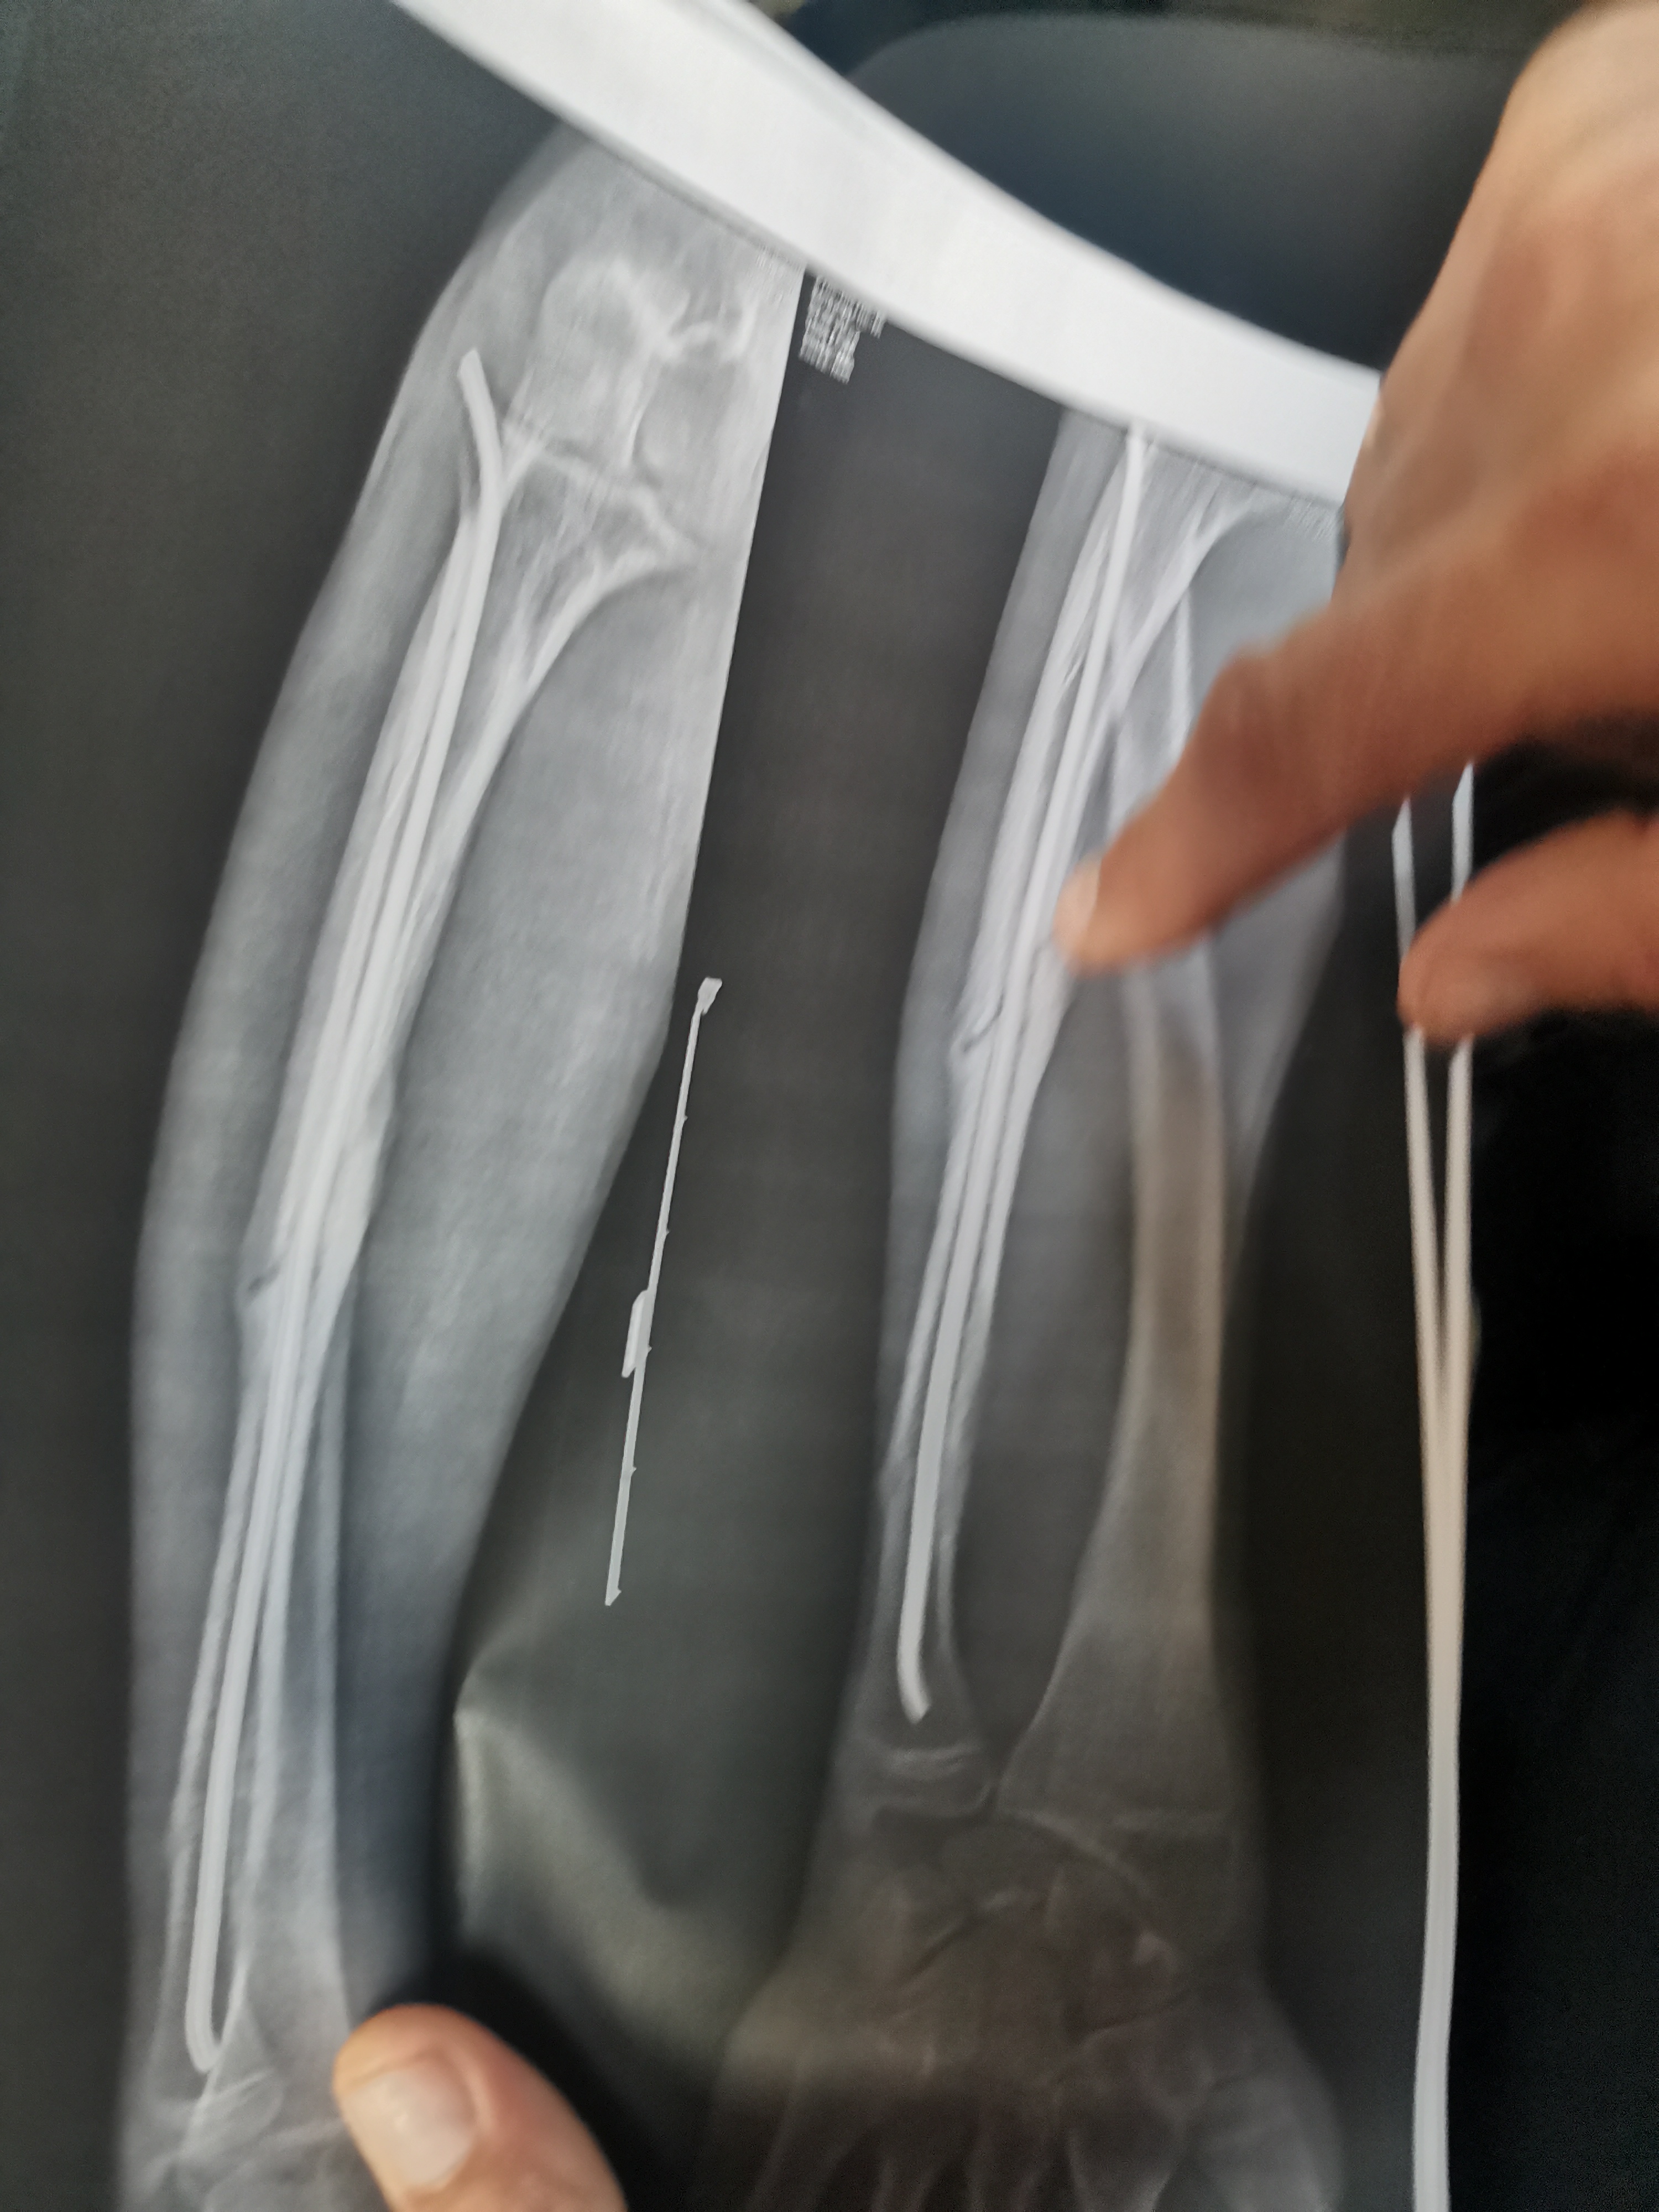

сломал руку анон 04/12/25 Чтв 22:39:24 1651111 Ответ

Всех приветствую, если выше написал всякую хуйню. То скажу честно зашёл сюда первый раз. И так, перейду к теме.

Мне 15 и я работал у мужика одного, хороший такой и в итоге когда он был в отъезде я, мой батя и пару друзей остались в ангаре, я решил почистить станок, а он был с щётками и там расстояние крайне маленькое, в итоге я его забыл отключить и когда решил убрать мусор мою руку зажевал.

3 перелома со смещением и раздроблена кость, доставали 2,5 часа, руку вообще не чувствовал, могут ли быть какие либо осложнения в будущем?

Аноним 20/12/25 Суб 00:17:11 1652698

>>1651111 (OP)

Могут быть, а могут и не быть, 50/50. Радуйся тому, что рука осталась, и даже все пальцы на месте. Будь осторожнее и впредь соблюдай технику безопасности.